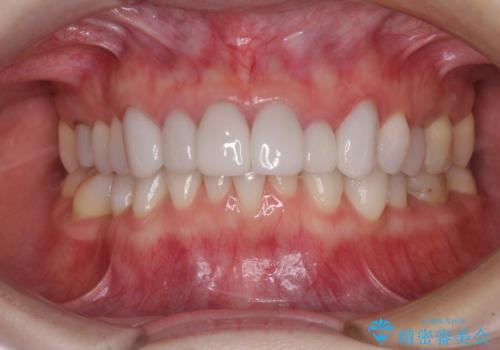

気にしていた歯並びをインビザラインで改善 セラミックも作り替えて綺麗な口元に

- 全体的なデコボコと、奥歯の欠損を放置した結果倒れ込んだ奥歯などを気にして来院された患者様です。

ワイヤー矯正の方が理想的な仕上がりとできる状態でしたが、上顎前歯にクラウンが装着されているため、インビザラインにて矯正治療を行うこととしました。

矯正治療自体はインビザラインで満足のいく仕上がりとなりました。

全顎的に満足のいく仕上がりとなりました。